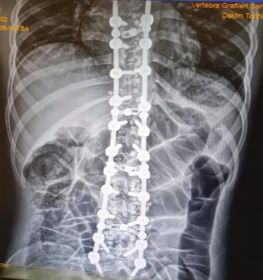

Omurga eğriliği yaşan insanlarda eğer eğrilik 40 dereceyi aşmış ise cerrahi operasyon ile tadavi edilir. Bu şekilde bir tedavi çok riskli ve zordur. Ardından ise mutlaka fizik tedavi ek olarak da korse tedavisi uygulanmalıdır.

Skolyoz hastalığı omurgaların dizilimindeki düzensizlik ve yamukluktur. Çoğunlukla çocuklukta görülen hastalık yetişkinlerde de az da olsa görülebilir. Sağa sola omurgalardaki çıkıntıların zamanla omurilik eğriliği bir hale getirdiği hastalıkta erken tanı çok önemlidir. İster yetişkin isterse çocuk olsun erken teşhis sonucunda fizik tedavi yöntemi işe yarar. Hastalık özellikle kişilerin günlük yaşantılarını etkileyen olumsuzluklar yaşatan ve yaşam kalitesini düşüren bir rahatsızlıktır. Geç kalınmadan tedaviye başlanmalıdır.